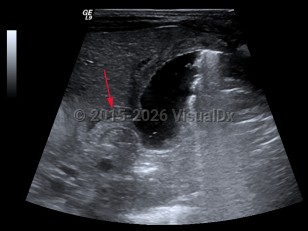

Hypertrophic pyloric stenosis

Hypertrophic pyloric stenosis (PS) is a narrowing of the pyloric lumen due to tissue hypertrophy and scarring. The resultant intestinal narrowing leads to gastric outlet obstruction and bowel obstruction. Although hypertrophic PS can very rarely occur in children and adults, this summary is focused on infantile hypertrophic PS. Patients present with emesis, usually within the first several months of life.

PS is predominantly seen in males (approximately 4:1) and presents typically at 2-7 weeks of life with nonbilious, postprandial projectile emesis and dehydration. Children of parents who had PS have a 20% increased risk of developing PS, suggesting a genetic component, although no clear genetic etiology has been identified.